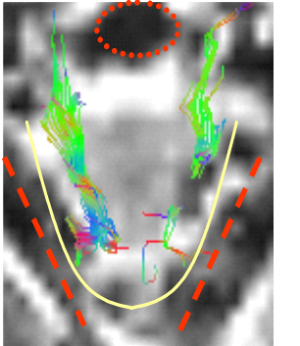

Velocity fields show motion from /s/ to /u/

Note anterior depression behind tongue tip in patient. The patient has a lateral lisp.

Fiber directions:

Green: anterior-posterior

Blue: superior-inferior

Red: lateral-media

Tongue is outlined in yellow

Pharynx is circled in red

Mandible is tracked in red